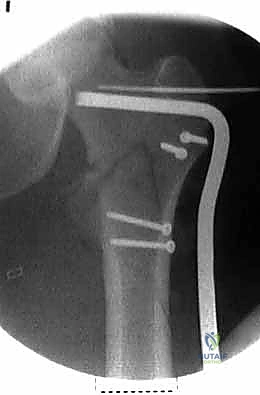

| وجه المقارنة | الشريحة والمسمار المنزلق (DHS - Dynamic Hip Screw) | المسمار النخاعي القريب (PFN - Proximal Femoral Nail) |

|---|---|---|

| آلية العمل | شريحة معدنية تُثبت على السطح الخارجي للعظم مع مسمار كبير يخترق عنق الفخذ. | مسمار من التيتانيوم يُدخل داخل التجويف النخاعي للعظم (من الأعلى) مع مسامير عرضية للتثبيت. |

| نوع الكسور المناسبة | الكسور المستقرة (Stable Fractures) ذات التفتت البسيط. | الكسور غير المستقرة (Unstable)، المفتتة بشدة، أو التي تمتد لأسفل العظم. |

| الشق الجراحي | شق جراحي جانبي أطول نسبياً (حوالي 10-15 سم). | جراحة طفيفة التوغل، شقوق صغيرة جداً (Minimally Invasive). |

| الميكانيكا الحيوية | يوفر ضغطاً ديناميكياً ممتازاً على موقع الكسر أثناء المشي. | يوفر دعماً ميكانيكياً أقوى لأنه يقع في مركز ثقل العظم (محور تحمل الوزن). |

| فقدان الدم | أكثر نسبياً مقارنة بالمسمار النخاعي. | أقل بكثير. |

| سرعة التعافي | ممتازة، ولكن قد تتطلب حذراً أكبر في الكسور غير المستقرة. | أسرع، ويسمح بتحميل الوزن في وقت أبكر في الحالات المعقدة. |

6. التثبيت النهائي (Locking)

لضمان عدم تحرك الغرسة، يتم تثبيتها بمسامير إضافية أصغر في جسم عظم الفخذ. هذه المنظومة الميكانيكية توفر ثباتاً استثنائياً يسمح للمريض بتحريك ساقه فور استيقاظه من التخدير.

مجموعة من الصور الإضافية التي توضح مراحل دقيقة من العمل الجراحي المعقد الذي يجريه الأستاذ الدكتور محمد هطيف لضمان أعلى درجات الدقة الميكانيكية الحيوية: